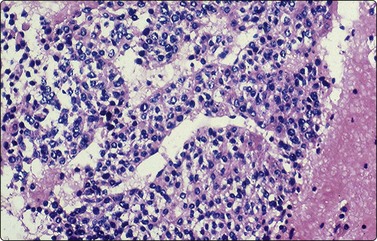

image

Fig. 17.18 Hepatoblastoma

Cell block preparation demonstrating small to medium-sized polygonal fetal-type cells with moderate amounts of granular cytoplasm and arranged in thick trabeculae (H&E, ×200).